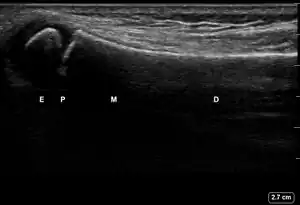

| # | Proper Technique for Image Acquisition and Interpretation | Ultrasound Image Meets Standard | Ultrasound Image Does Not Meet Standard |

|---|---|---|---|

| 1 | ![]() |

![]() |